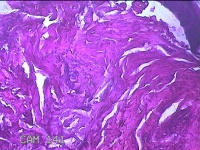

臀部肿物

性别

女

年龄

32岁

临床诊断

脂溢性角化病;皮肤感染

一般病史

颈部臀部丘疹数年。

标本名称

大体所见

灰白粉红色带皮肤样肿物1.8x0.5x0.2cm一个,表面糜烂。

图2